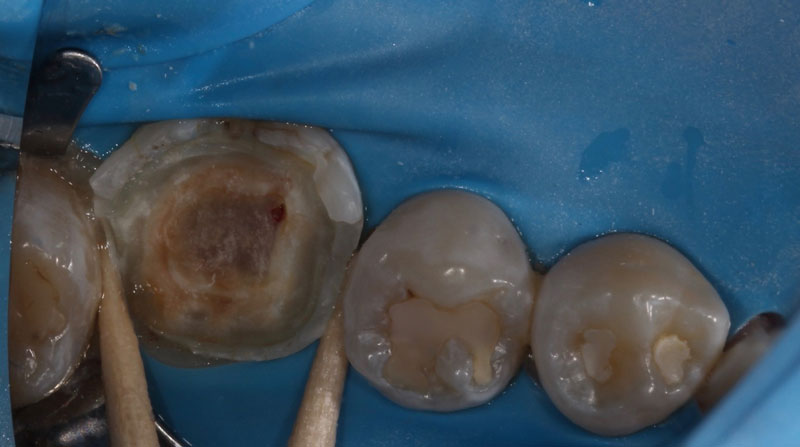

Pulp capping can be divided into two categories: indirect pulp capping and direct pulp capping. For an indirect pulp cap, a carious lesion approaches the pulp tissue, but a pulp exposure does not occur. With a direct pulp cap, the pulpal tissue is exposed, and a medicament is placed over the exposure. Both procedures have historically been controversial. However, with a greater focus on conservative dentistry and more research on pulp capping, this topic is being discussed more frequently.

A direct pulp cap exposes a portion of the pulp tissue. This can occur due to traumatic or carious pulp exposures. In the past, when a tooth’s pulp was exposed, it almost always led to endodontic therapy. However, direct pulp capping may be feasible in specific clinical situations with modern materials that can help maintain pulp vitality, such as MTA and similar bioceramics.

Another key factor is isolation. In general, when a carious lesion is near the pulp chamber, it is advised to utilize rubber dam isolation. This helps minimize any contaminants in the preparation and simplifies the transition to endodontic therapy if pulp exposure occurs, which necessitates it.